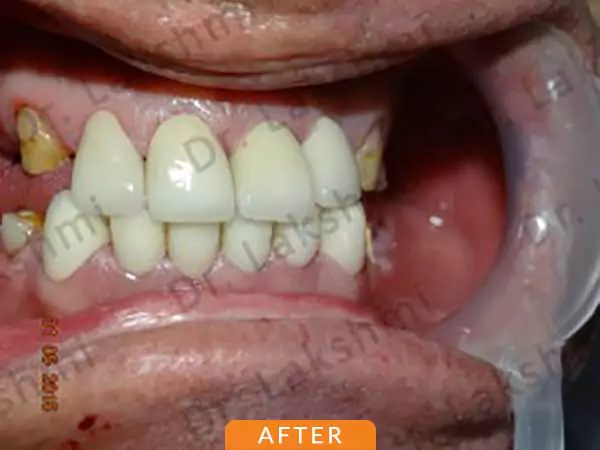

Dental implants have come to define modern dentistry in the last few decades. Dental implants are cemented to the jawbone and an abutment is used as a support for the dental crown that is placed over it. There are a single piece, two-piece and three-piece abutments available for implants. Titanium fuses naturally with the jawbone and that makes it a perfect fit as an implant. There are several dental implant techniques available to opt from, for a patient. The freedom to opt also depends on the condition of the jawbone and the gum.

Requires the placement of a single dental implant (either 2 stage or 1 stage) in the region of the missing tooth, followed by a crown (artificial tooth) over

Treatment Duration: 2 stage dental implants: The replacement is completed in 2 stages which are spread over an interval of minimum 3 months. The first stage involves the placement of the implant and requires one to two sittings,Temporary Crowns will be given to the patient. The second stage involves the placement of the artificial tooth (Permanent crown).

1 stage dental implant: Requires just one stage for the placement of the implant and crown(Permanent Crown).